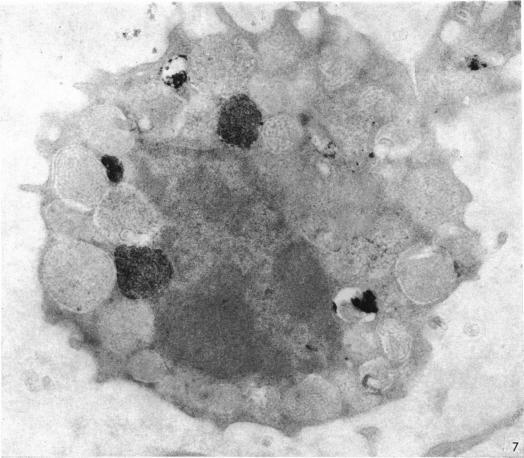

Detailed morphologic and enzyme cytochemical analysis was carried out by electron microscopy on granules of mature granulocytes obtained from the circulating chicken blood. Heterophils possessed three types of granules: large, rod-shaped, dense (Type I); medium sized, oval, light (Type II); and small-core (Type III). Acid phosphatase activity was present in Type I granules, but peroxidase and alkaline phosphatase were not demonstrable. The cytochemical nature of Types II and III granules remains unknown. Eosinophils contained only one type of granule, which was circular and had electron-opague contents. Both peroxidase and acid phosphatase, but not alkaline phosphatase, were present, indicating that the granules are lysosomes like the granules of mammalian eosinophils. Basophils possessed two types of granules, the characteristic large basophilic granules (Type I) and small dense granules (Type II). Acid phosphatase activity was found in only a small proportion of Type I granules: peroxidase and alkaline phosphatase were not demonstrable.

运用电子显微镜对取自鸡循环血液中的成熟粒细胞的颗粒进行了详细的形态学和酶细胞化学分析。嗜异性粒细胞有三种类型的颗粒:大的、杆状的、致密的(I型);中等大小的、椭圆形的、浅色的(II型);以及小核心的(III型)。I型颗粒存在酸性磷酸酶活性,但过氧化物酶和碱性磷酸酶未得到证实。II型和III型颗粒的细胞化学性质仍然未知。嗜酸性粒细胞仅含有一种类型的颗粒,呈圆形且内容物电子密度高。过氧化物酶和酸性磷酸酶都存在,但碱性磷酸酶不存在,这表明这些颗粒是溶酶体,类似于哺乳动物嗜酸性粒细胞的颗粒。嗜碱性粒细胞有两种类型的颗粒,即特征性的大嗜碱性颗粒(I型)和小致密颗粒(II型)。仅在一小部分I型颗粒中发现酸性磷酸酶活性:过氧化物酶和碱性磷酸酶未得到证实。